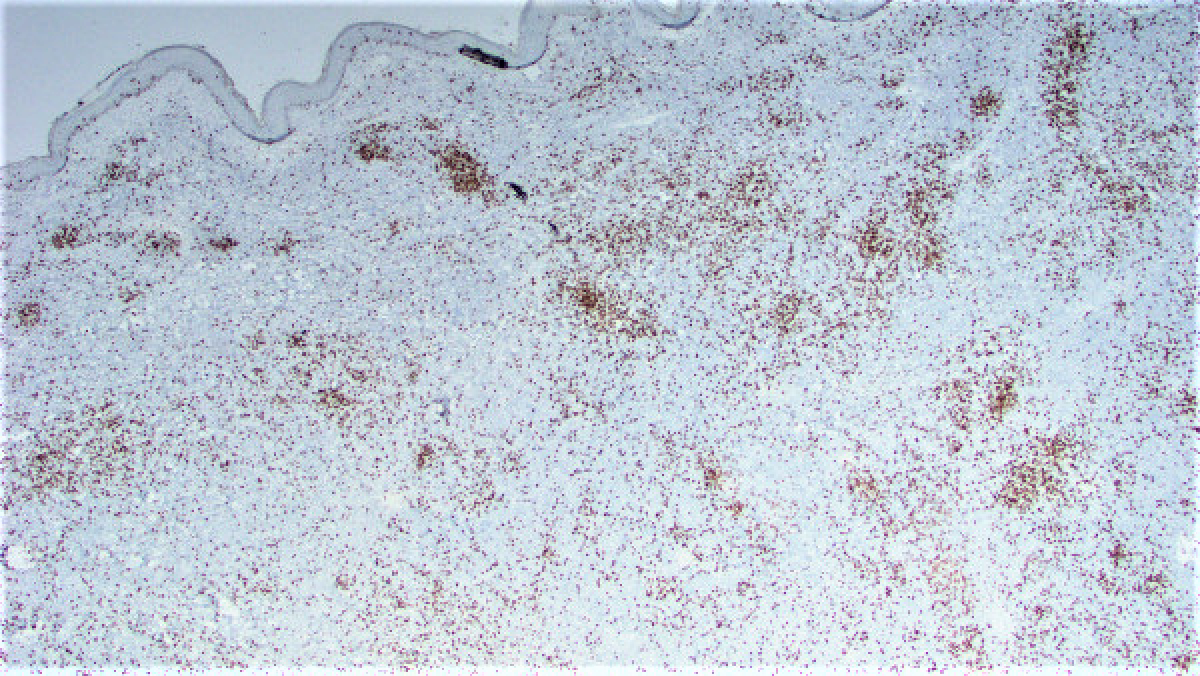

Three months ago the patient presented with a pink rash on the upper right arm. This was treated with topical steroids and the biopsy of that lesion revealed a reactive lymphoid proliferation. One month later the patient noticed a raised lesion on her upper right arm. An excisional biopsy of this lesion was performed. This biopsy revealed a vaguely nodular dermal infiltrate composed of a mixture of small cells with a high nuclear:cytoplasmic ratio and some larger cells with a plasmacytoid appearance (Figures 1 and 2). Immunohistochemical stains were performed and revealed both populations of cells to diffusely express CD20 (Figure 3) while negative for CD23 (Figure 4) and BCL-6 (Figure 5). There were scattered CD3 lymphocytes (Figure 6). Ki-67 was low (~20-30%), but elevated within residual germinal centers. Flow cytometry revealed lambda-restricted B cells, negative for CD5 and CD10.